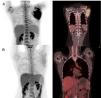

While receiving the second cycle of blinatumomab, she complained of a worsening of her left shoulder mass and noted a new left cervical lymphadenopathy, measuring 1.5cm, denoting progression of the extramedullary disease. After this cycle, a new BM aspiration showed no blasts and the MRD evaluation remained negative. A new 18FDG-PET-CT demonstrated progressive extramedullary disease (Figure 2).

Considering this, we decided to try IO. The drug was administered in our outpatient clinic as monotherapy, as originally described (0.8mg/m2 on day 1 and 0.5mg/m2 on days 8 and 15).5 After two cycles of IO, the patient and the medical team noticed a clinical reduction in the scapulary tumor. Local irradiation of 30Gy was delivered as consolidation. After IO and radiotherapy, a new PET-CT was performed, demonstrating a complete remission status, along with MRD negativity found in the BM assessment (Figure 2). Thus, she was referred to haploidentical allogeneic stem-cell transplantation (SCT), but died prematurely from transplantation-related complications – thrombotic microangiopathy and sepsis.